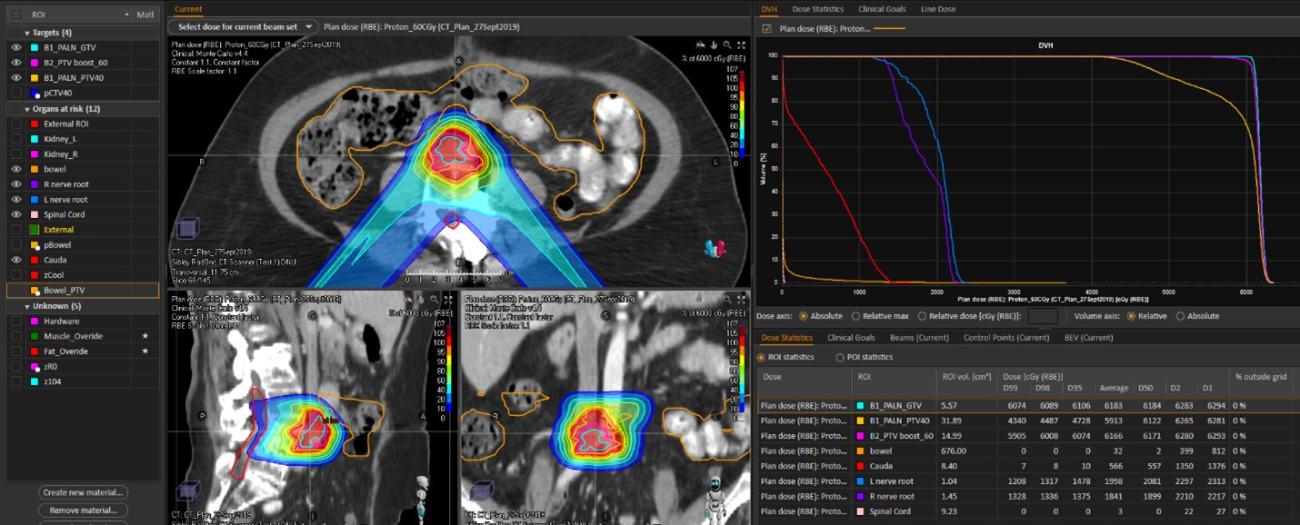

Case 2 | RECURRENT ENDOMETRIAL CANCER IN PARAAORTIC NODE

Patient Case

Patient is a 76-year-old woman with a hx of breast ca and stage IIIC1 high grade uterine carcinosarcoma initially diagnosed in 2013 treated with total abdominal hysterectomy, bilateral salpingo-oopherectomy, and lymph node dissection. Pathology demonstrated <50% myometrial invasion, lymphovascular space invasion and evidence of 6/6 involved right pelvic lymph nodes and 2/5 involved left pelvic lymph nodes). She went on to receive 6 cycles of chemotherapy followed by external beam radiation with intensity modulated radiation therapy (IMRT) to 45 Gy and vaginal brachytherapy 7 Gy x 3. She then had a biopsy proven recurrence in a para-aortic node 4 years later.

Treatment

She was treated with proton therapy due to prior radiation to reduce dose to organs at risk.

Proton Plan: Isodose, Dose volume histogram, Dose Statistic